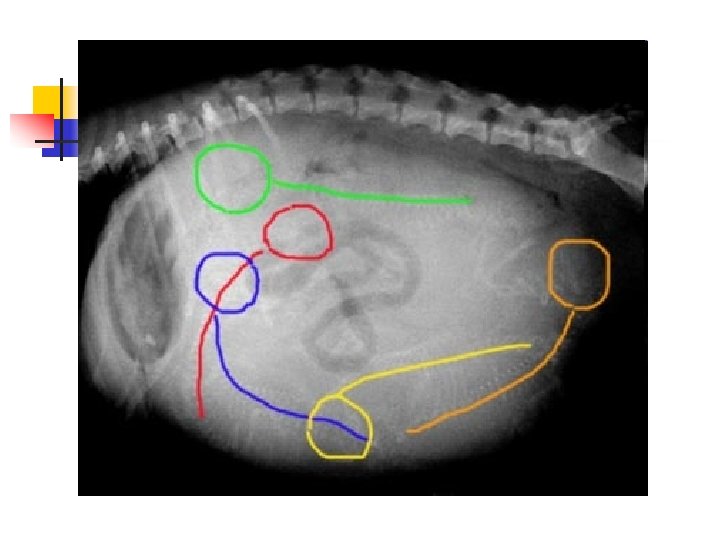

How Many Puppies? n n This dog's owner knew she was pregnant and was hoping for a big litter. Can you count how many puppies she is expecting? Here's a hint: the little puppy skeletons are visible. Try to count heads and backbones. It's harder than it looks because the puppies overlap each other!

Here is the answer: n n There are five puppies. I have outlined the heads and backbones in different colors to point them out.